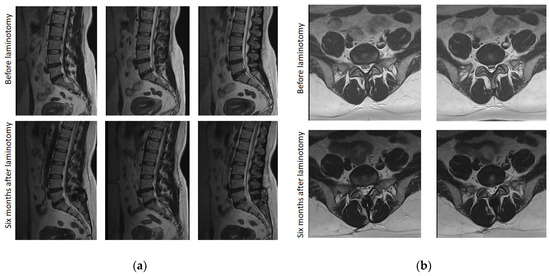

2.3.8. Magnetic Resonance Imaging Founds

3.8. Magnetic Resonance Imaging Examination